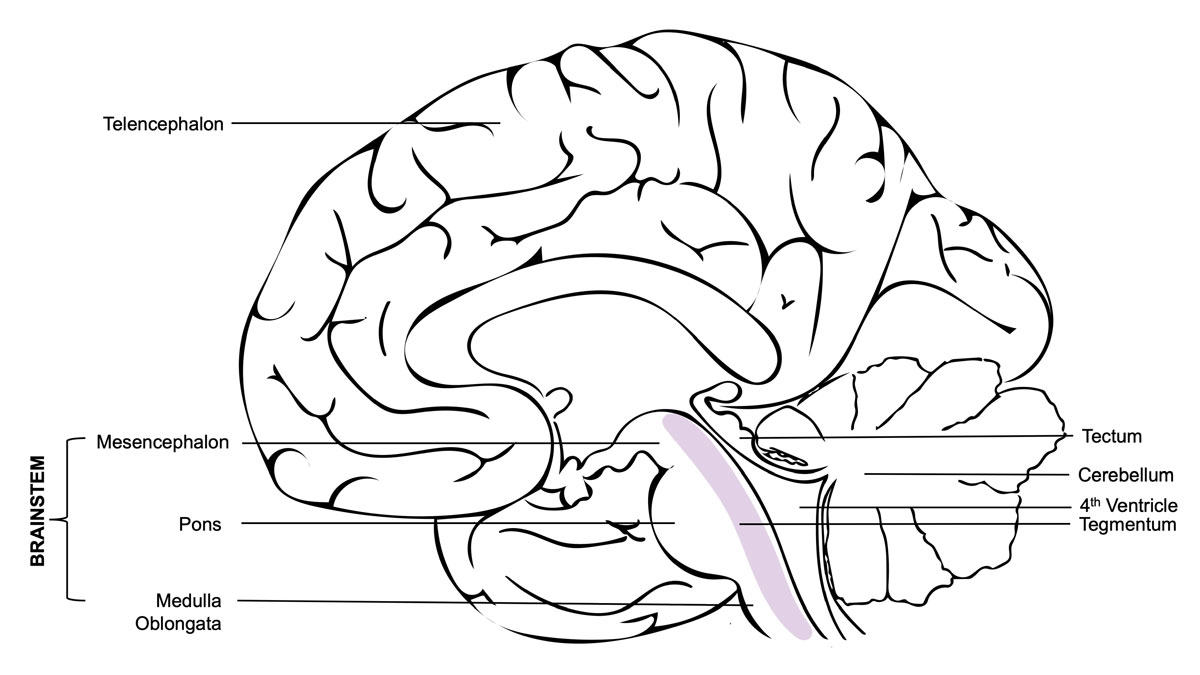

Different kinds of classifications have been proposed for brainstem haemorrhages, mostly based on the axial CT features of the exact localisation and anatomical spread [11, 14, 15, 21]. Some classifications include tegmental parts (mesencephalon), and others concentrate solely on pontine haemorrhages (fig. 2). In a study of 62 cases in 1992, Chung et al. classified brainstem haematomas into four types: (1) the “massive” type, which they defined by its bilateral spread into both the basis pontis and the tegmentum; (2) the “bilateral tegmental” type, which occupied the bilateral tegmentum only; (3) the “basal-tegmental” type, which was localised in the junction between the basis pontis and the tegmentum bilaterally; and (4) the “small unilateral tegmental” type, which referred to haematomas located exclusively in the unilateral tegmentum [14]. The survival rates for the types were shown to be 7.1%, 14.3%, 26.1% and 94.1%, respectively [14]. Other groups (Rabinstein et al. and Balci et al.) tried to simplify this classification into three types by combining the basal and bilateral tegmental types in one group [16, 19]. However, a 1999 study by Fong et al. with 39 cases found a survival rate of 30.8% for the bilateral tegmental type and a 100% survival rate for the basal-tegmental type. This suggests that grouping the two locations together may not be justified [17]. In general, previous studies agree that basal-tegmentum and small unilateral tegmentum haemorrhages are associated with more favourable outcomes, while almost all massive haemorrhages and most bilateral tegmental haemorrhage cases are prognostically poor [16–18].

Figure 2 The mesencephalon, pons and medulla oblongata all belong to the functional unit that we call the brainstem. It is situated in the posterior cranial fossa and its ventral surface lies on the clivus. The brainstem is a very compact and dense region packed with cranial nerve nuclei and neurons from the reticular formation. Damage to the brainstem is therefore often life-threatening. Even small lesions can destroy cardiac and respiratory centres, disconnect the forebrain motor areas, or destroy higher centres of consciousness, perception and cognition. The tegmentum (Latin for “covering”) is an anatomical name for the area located between the ventricular system (4th ventricle) and the basal structures of the brainstem. It contains the rostral end of the reticular formation.